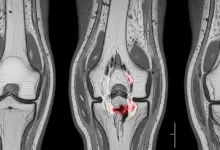

A osteotomia no joelho valgo é uma cirurgia de realinhamento indicada em casos específicos, quando o desvio do eixo do membro passa a concentrar carga em excesso na parte lateral do joelho e começa a gerar dor, limitação funcional e desgaste progressivo.

No joelho valgo sintomático, a meta é redistribuir a carga que está passando de maneira exagerada pela região lateral do joelho.

A cirurgia é considerada quando existe relação clara entre desalinhamento, dor e sobrecarga no compartimento lateral do joelho.

- Desgaste localizado no compartimento lateral.